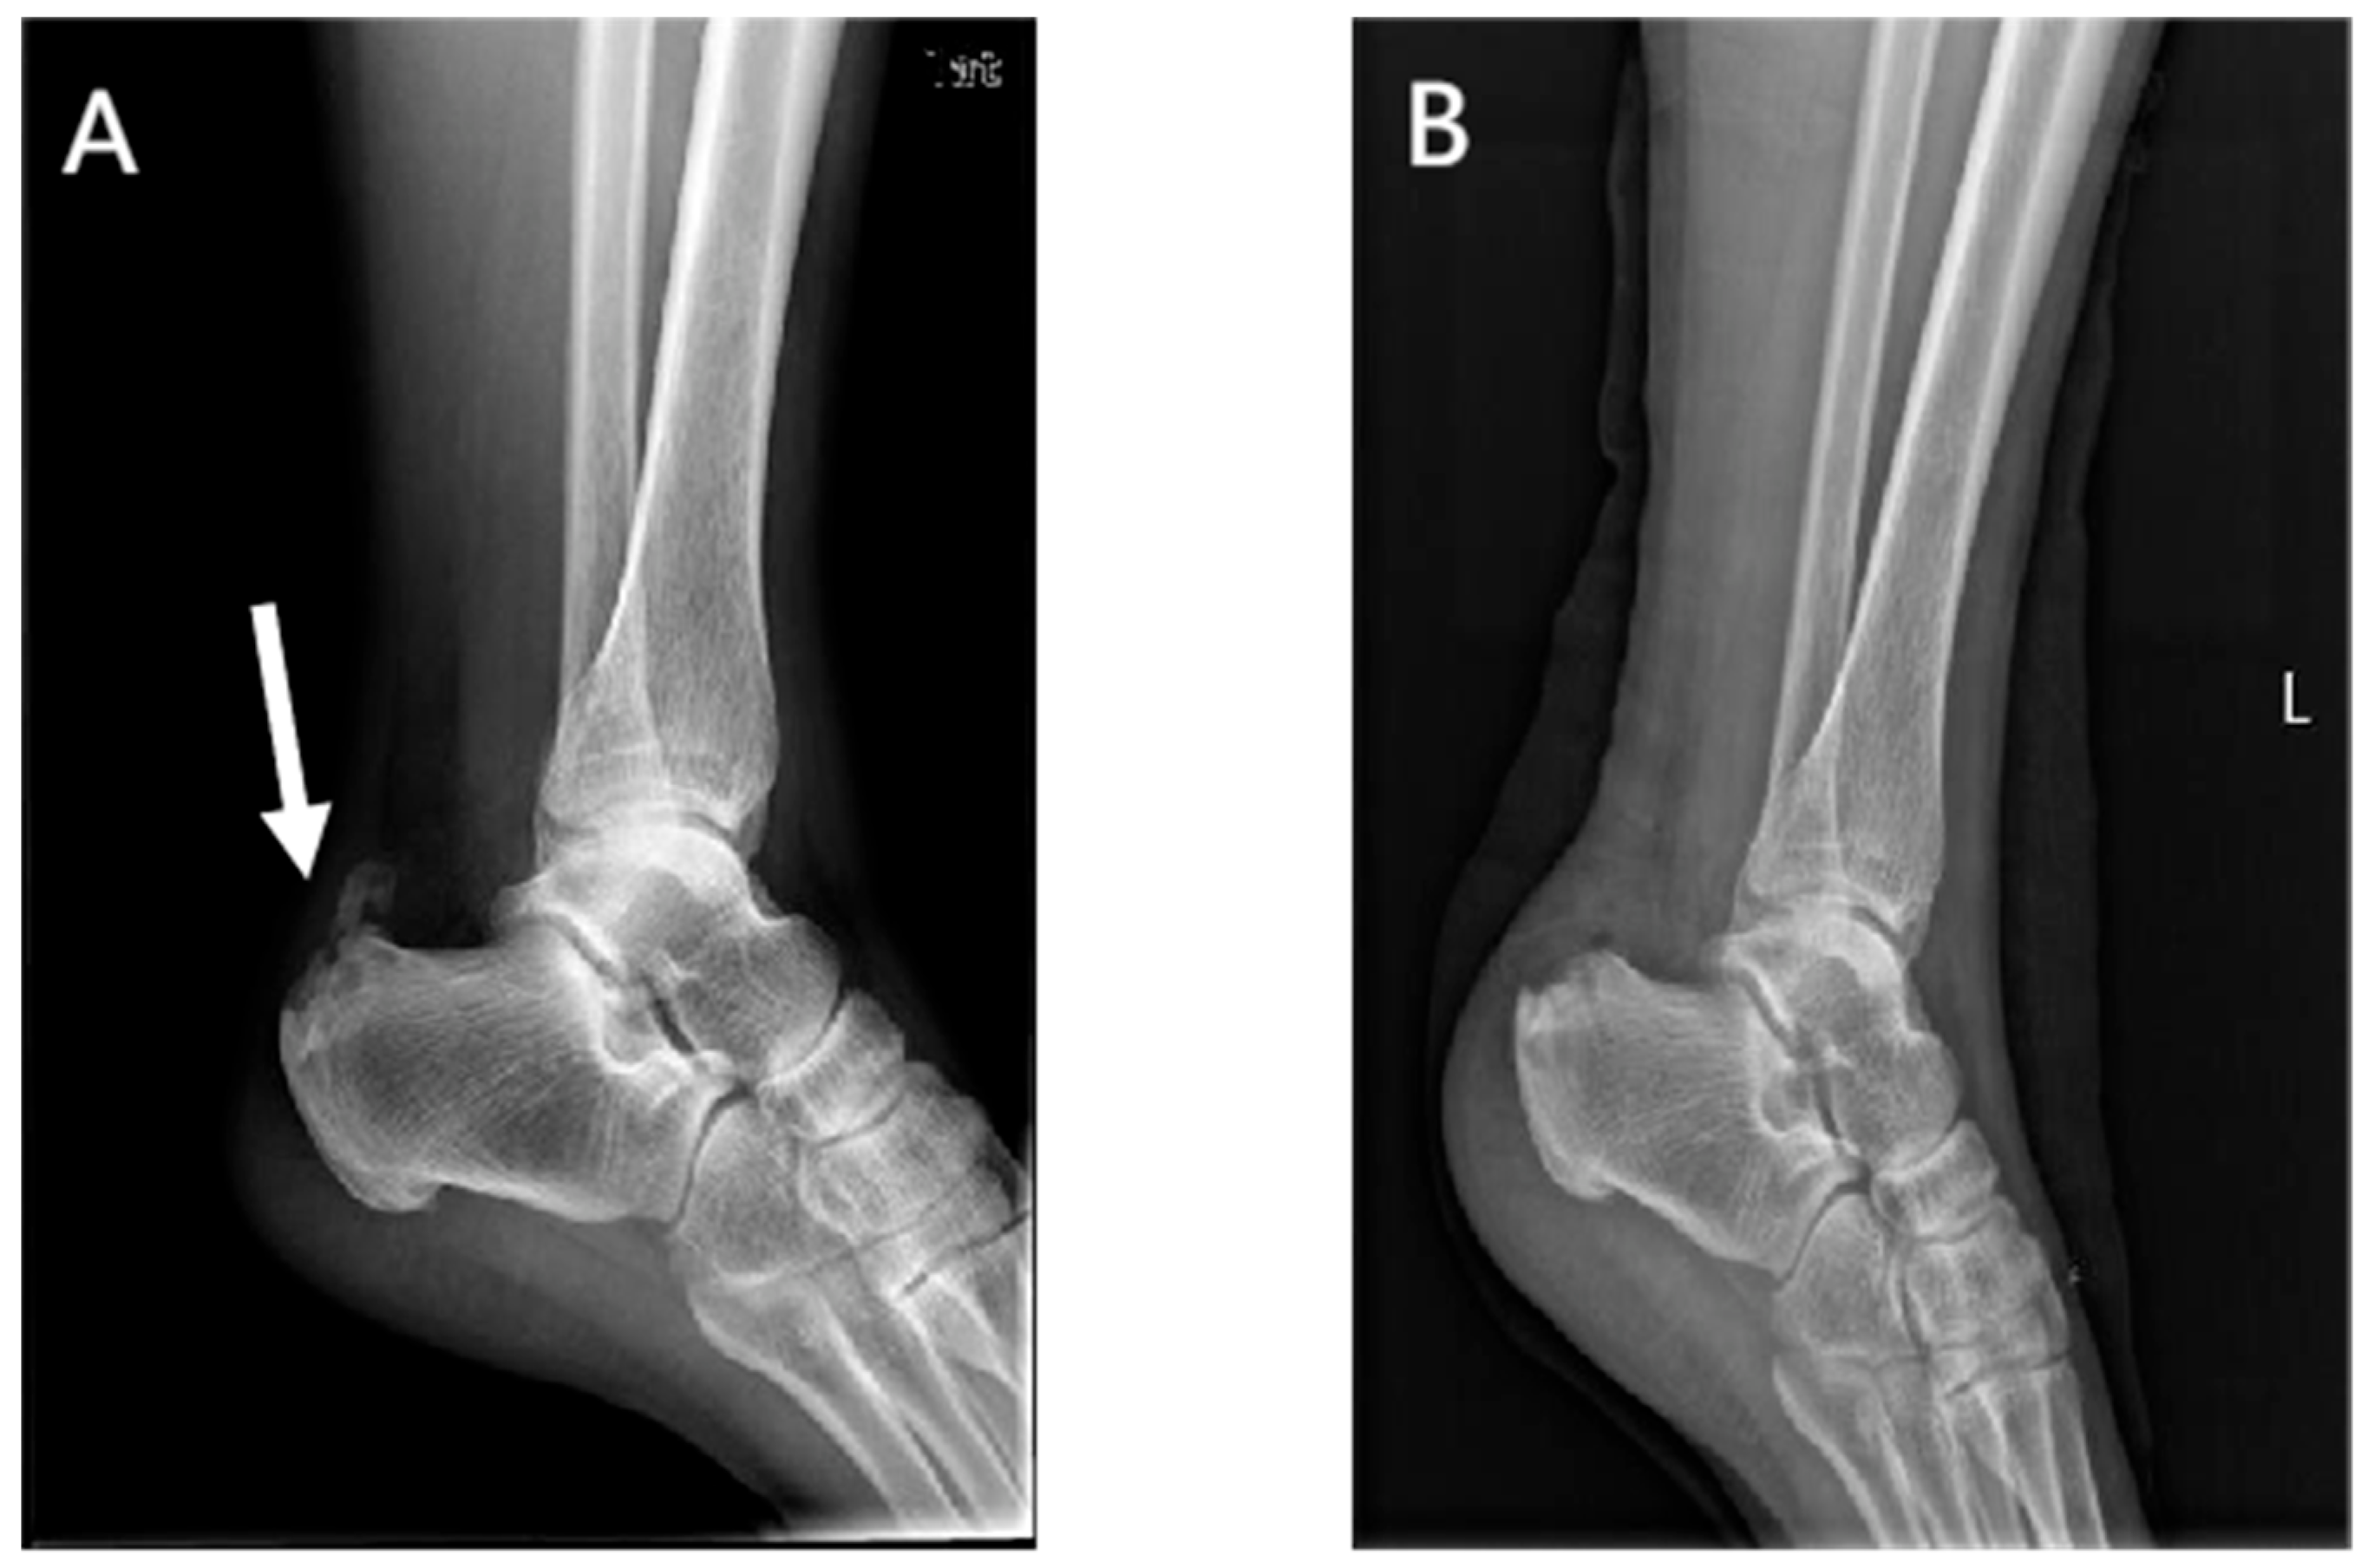

Lateral radiographs of the ankle 1 day postoperatively showed the complete removal of the calcific lesions in the Achilles tendon (Figure 3 and Figure 4). No loosening or fracture of the anchors occurred during the follow-up. All the surgical wounds healed well with no infection, scar, or dehiscence. No severe complications occurred, such as sural nerve injury, saphenous vein injury, or venous thrombosis. No patients experienced Achilles tendon rupture, contracture, or adhesion. There was no significant difference in the range of motion between the affected ankles and the contralateral ones (dorsiflexion: 23.7 ± 1.5 vs. 23.8 ± 1.9 degrees, p = 0.503; plantar flexion: 38.8 ± 2.2 vs. 39.3 ± 2.1, p = 0.080). At the last appointment, all 25 patients were asymptomatic and had returned to their pre-injury levels of activity and mild sports.

Figure 3.

Preoperative (A) and postoperative (B) lateral radiographs of the ankle in the internal brace group. Arrow, a calcific lesion in the Achilles tendon.